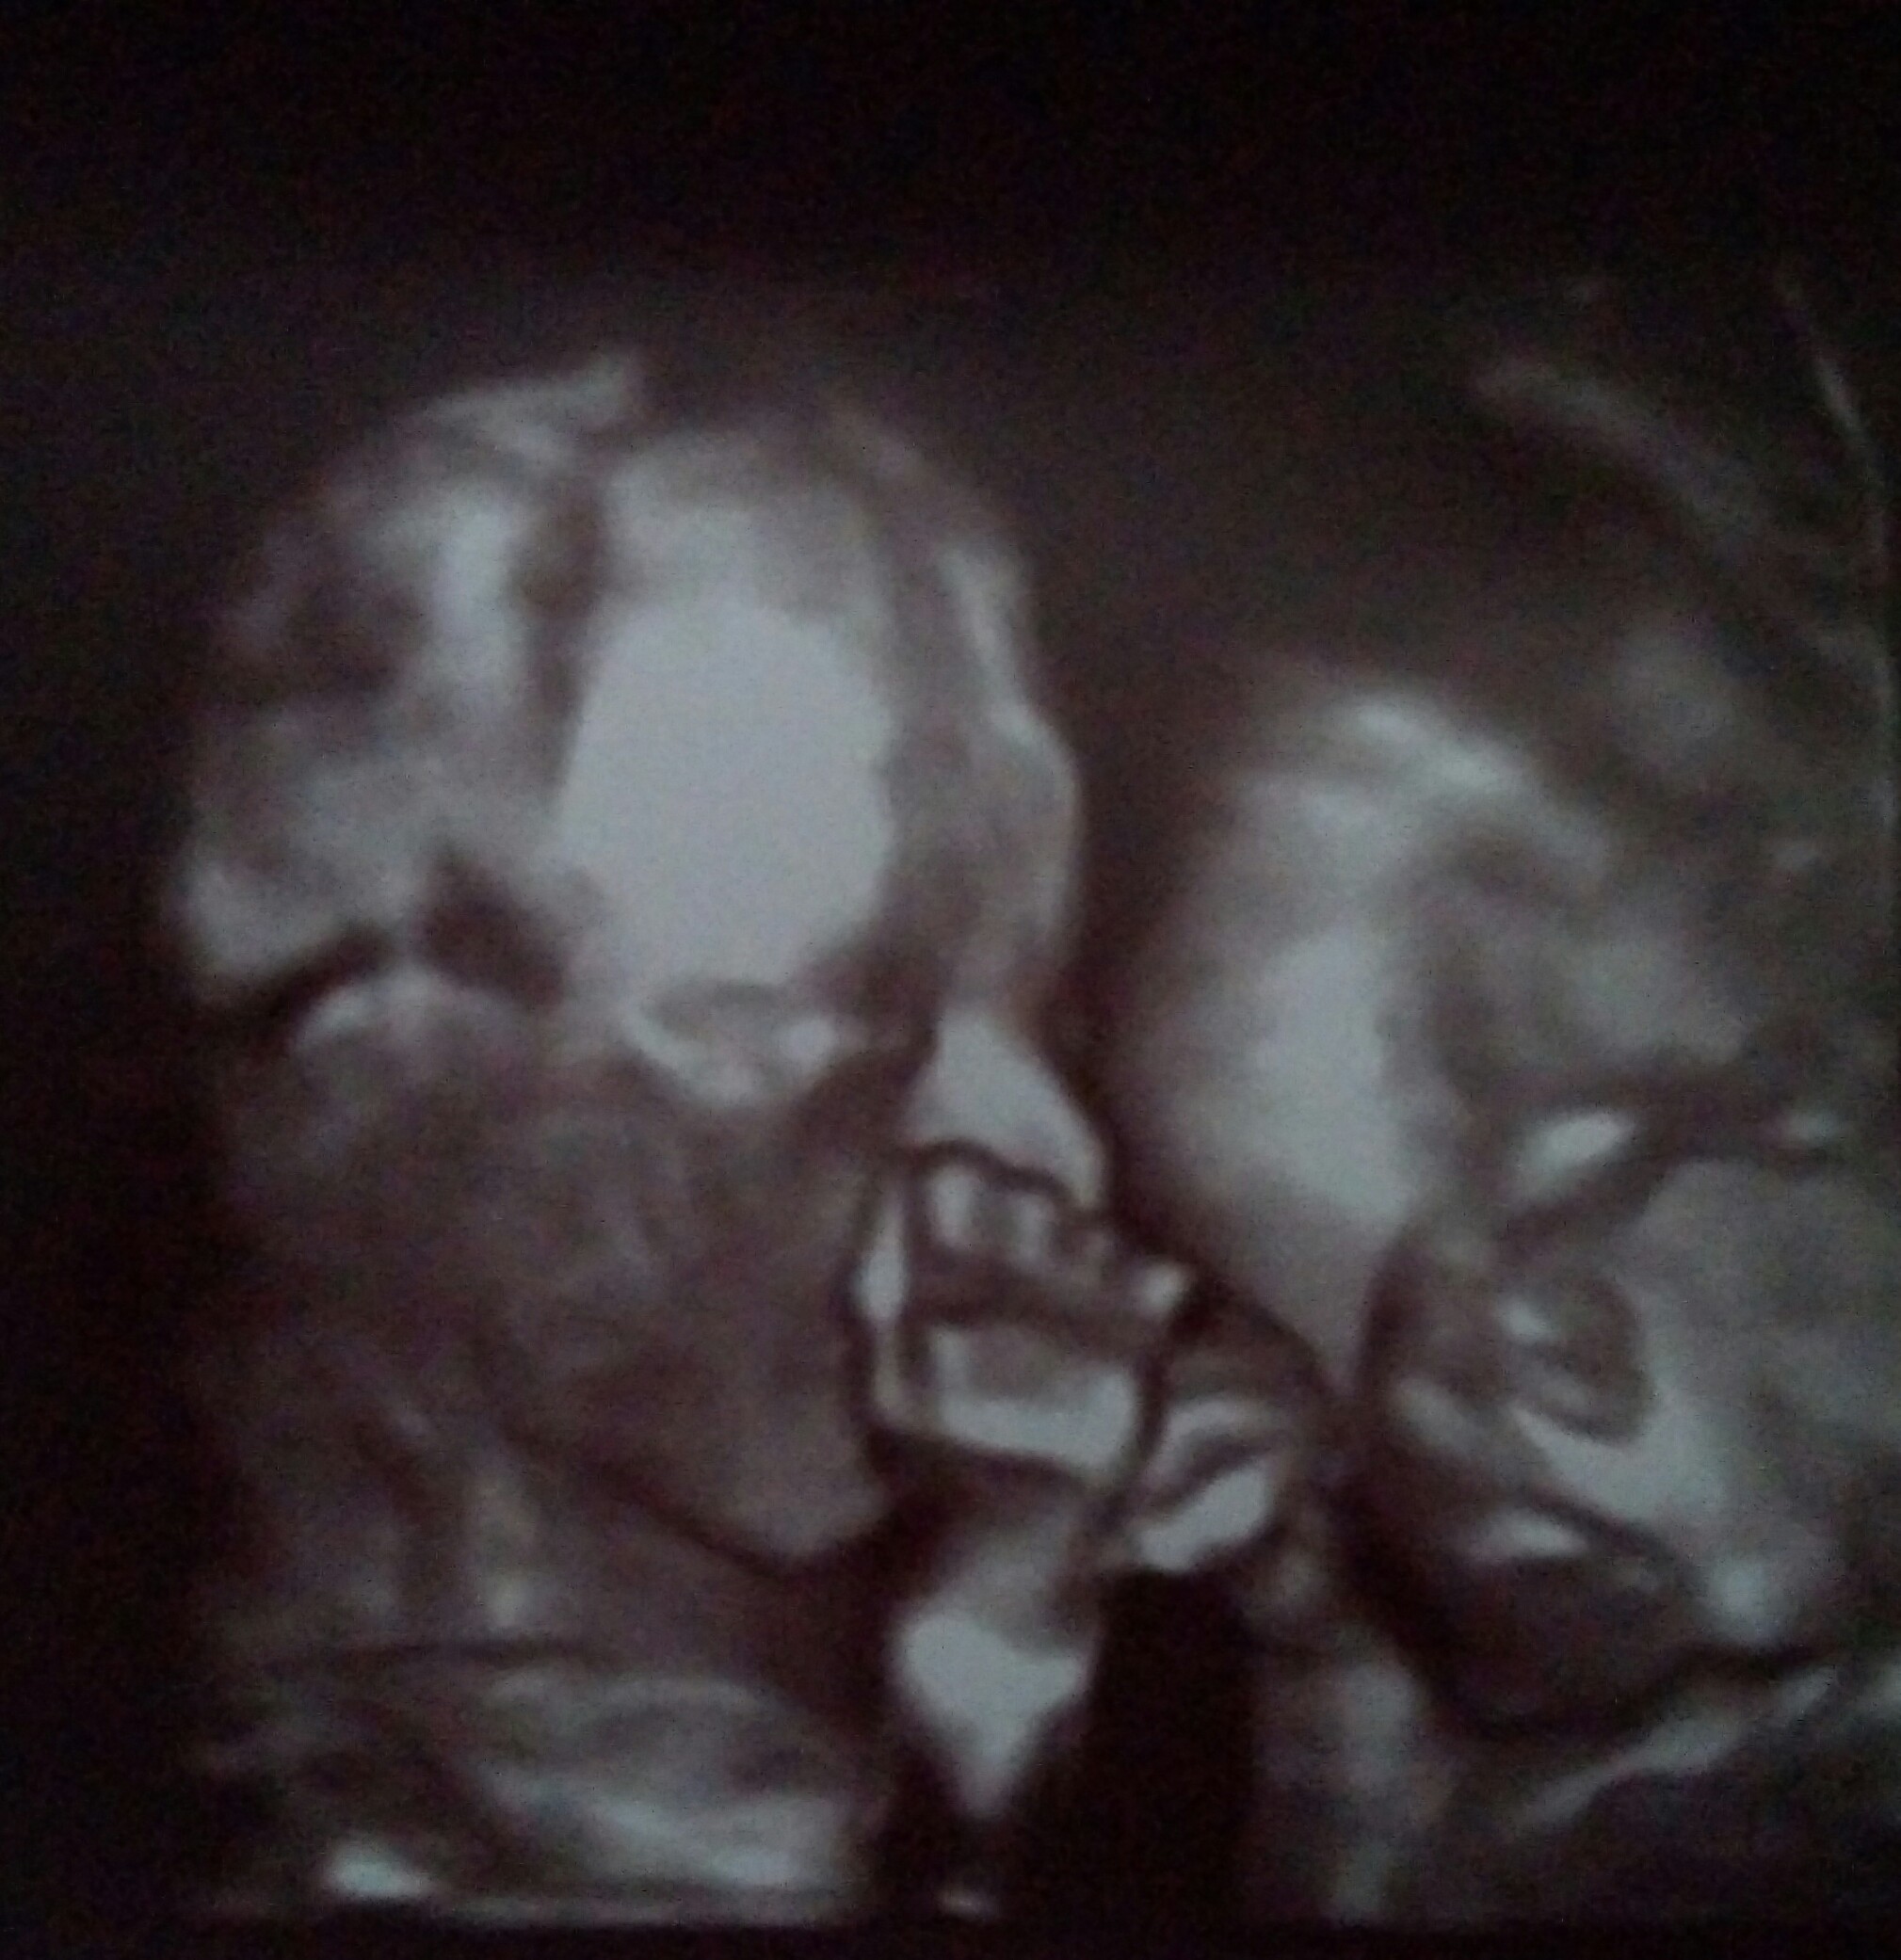

Hej dziewczyny. Nie wiem jak to się stało ale źle się w kalendarz wpisałam bo to połówkowe miałam dzisiaj. Z dzieciakami wszystko ok :-) Rosną jak na drożdżach juz mają po 413 i 427g...

Załączniki

• IMG_20170807_102851~2.jpg

IMG_20170807_102851~2.jpg

479,2 KB · Wyświetleń: 126

• IMG_20170807_102900~2.jpg

IMG_20170807_102900~2.jpg

455,3 KB · Wyświetleń: 118